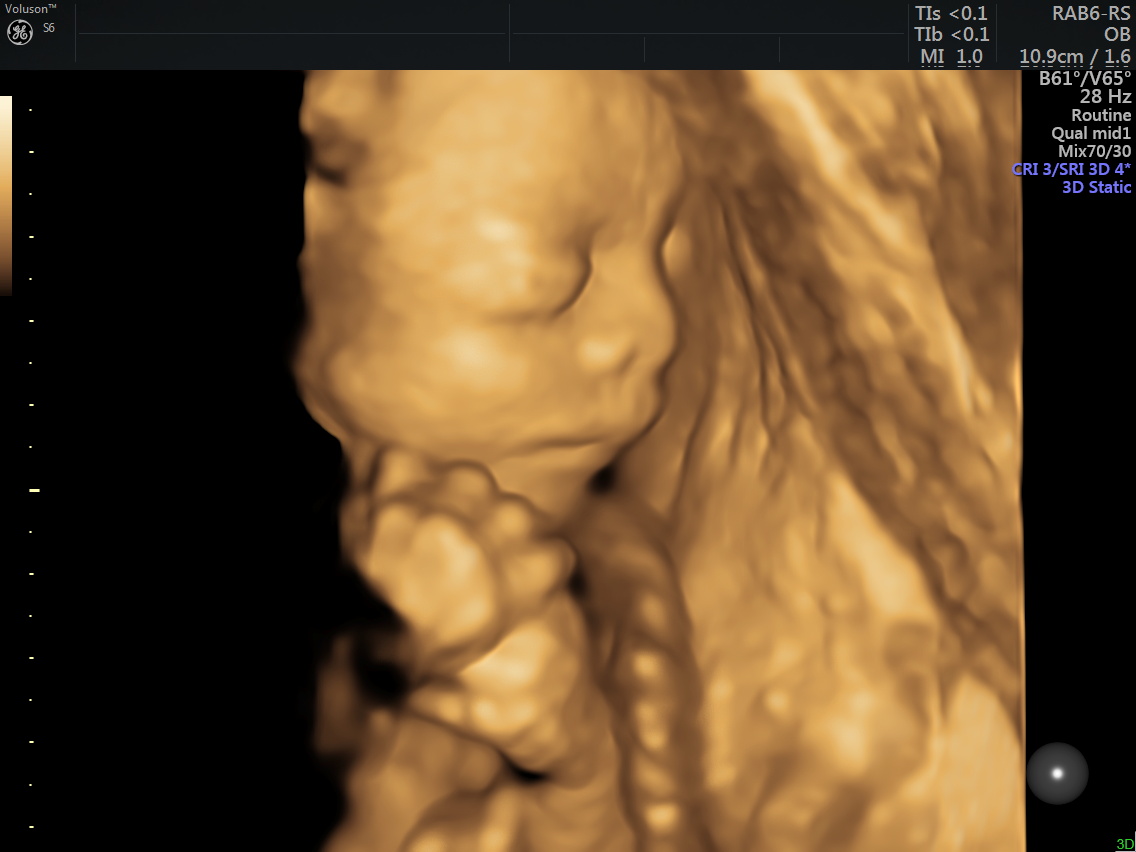

4D (dört boyutlu), Renkli, Ayrıntılı Gebelik Ultrasonu

4 boyutlu renkli ultrason ve 3 boyutlu ultrason aslında aynı anlama gelmemesine rağmen halk arasında , ayrıntılı ultrason, detaylı ultrason , ileri düzey ultrason, anomali ultrasonu , 2. basamak ultrason, ikinci düzey ultrason, renkli ultrason , büyük ultrason , genetik ultrason ile aynı anlamda kullanılmaktadır.

4 boyutlu renkli ultrason cihazı ile çok erken dönemde cinsiyet, yarık dudak, yarık damak, eksik parmak, beyin ve omurilikten kaynaklanan rahatsızlıkların erken tanısı konulabiliyor.